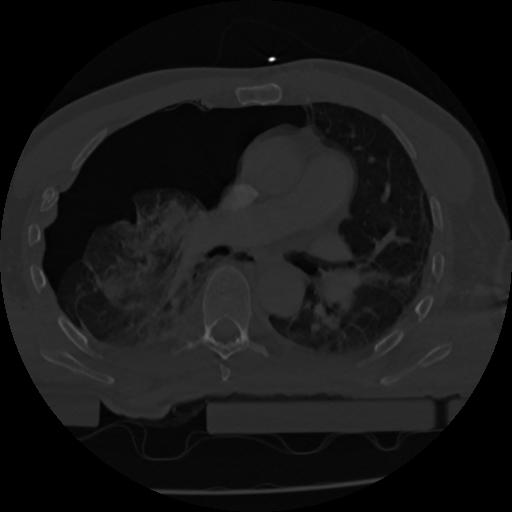

22 ANGIO,CE,Vol,0.5,ANGIO,,